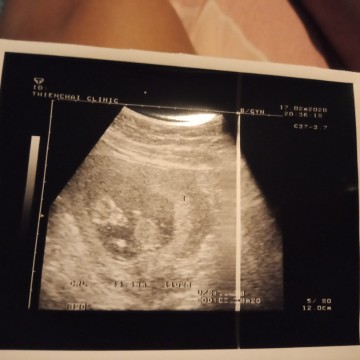

แม่ๆคนไหนรุ้บ้างค่ะ พึ่งซาวไปเมื่อวันที่17/02 อยากรุ้ว่าแบบนี้น้องสมบูรดีมั้ยค่ะ 11W5D

ยังดูไม่ได้ค่ะ ต้องรอให้น้องมีอวัยวะครบก่อน ต้องรอให้อายุครรภ์มากกว่านี้หมอถึงจะบอกได้ค่ะ